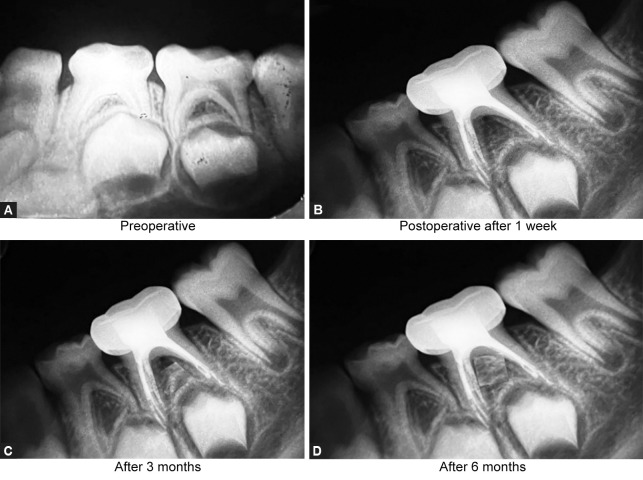

Materials and methods: The present study was conducted in 60 children of age group 4-10 years requiring multiple visit pulpectomy for their primary molars. Selected teeth were randomly divided into three groups: group I - calcium hydroxide with Ocimum sanctum, group II - calcium hydroxide with Curcuma longa, and group III - calcium hydroxide with Aloe barbadensis miller. Clinical and radiographic evaluation was done among the groups at intervals of 1 week, 3 months, and 6 months.

Results: There was no significant difference in the clinical and radiographic success rate among the groups.

Conclusion: Among the three groups, calcium hydroxide with Ocimum sanctum group showed a higher success rate and that with Aloe barbadensis miller group showed the least success rate.